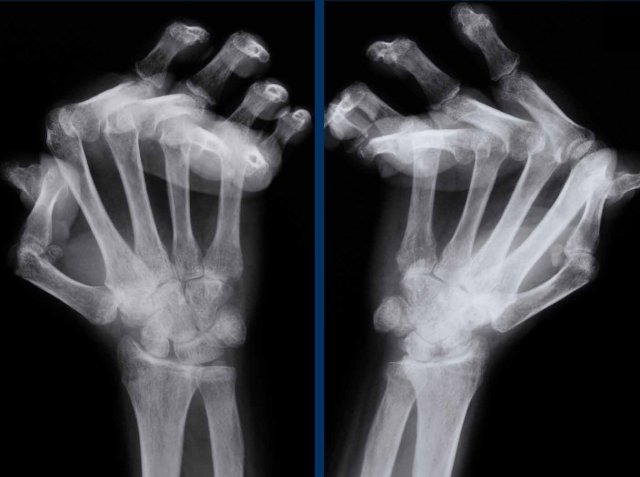

Ball catcher view of the hands in a patient with erosive osteoarthritis.

There is bilateral extensive damage to the IP joints.

Note the symmetrical distribution and sparing of the MCP joints.

Typical gull-wing appearance of the DIP-joints, also known as seagull erosions or sawtooth appearance.

This is classically seen in erosive osteoarthritis, but has also been reported in psoriatic and rheumatoid arthritis.